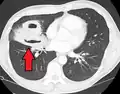

Pulmonary abscess on CT scan -

| Computed tomography (CT) scan of chest showing bilateral pneumonia with abscesses, effusions, and caverns. 37-year-old male. | |

Lung abscesses are often on one side and single involving posterior segments of the upper lobes and the apical segments of the lower lobes as these areas are gravity dependent when lying down. Presence of air-fluid levels implies rupture into the bronchial tree or rarely growth of gas forming organism.